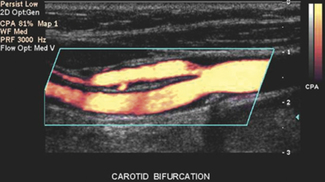

Power Doppler is also referred to as energy Doppler, amplitude Doppler and Doppler angiography. It is a color flow imaging technique that maps the magnitude, i.e. power, of the backscattered Doppler signal rather than the Doppler shifted flow velocities. The instantaneous signal strength contained in the Doppler signal is calculated and superimposed onto the B-mode image as illustrated in Figure 11.16. Its effect is to provide a map of areas of perfusion, by displaying the amplitude of red blood cells in an area.

image

Fig. 11.16 Power Doppler image of the carotid bifurcation

Power Doppler does not display the relative velocity and direction of blood flow as is the case with color flow imaging. Power Doppler uses a single color scale and maps increasing signal strengths to increased luminosity. It is often used in conjunction with frame averaging to increase sensitivity to low flows and velocities.